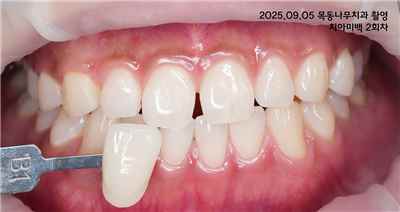

치아 변색 외부 요인